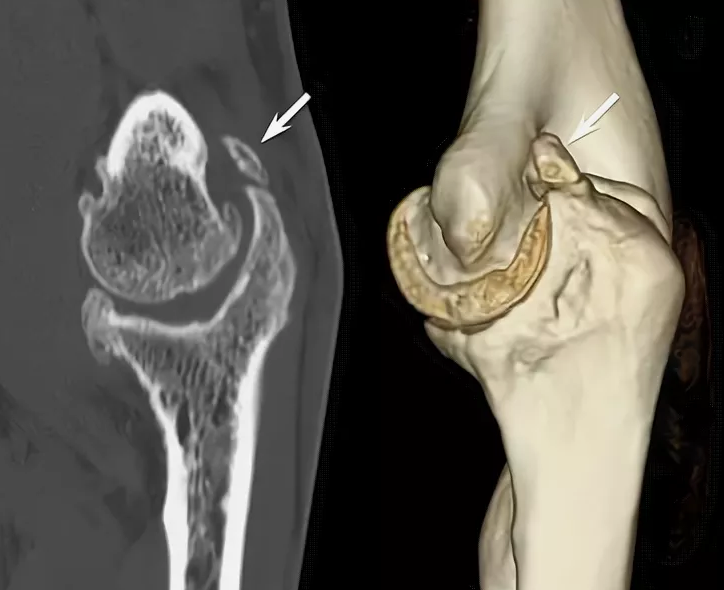

Деформацией считали наличие оссификатов, локализованных в ямках

дистального отдела плечевой кости, что подтверждалось по данным

компьютерной томографии (КТ).

При помощи КТ с трехмерной реконструкцией проводилась предоперационная

подготовка, включающая топографию изменений суставных поверхностей и

параартикулярной области.